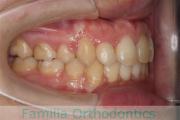

口元に力が入ってしまうのを治したいということで来院されました。上の側切歯が小さいのですが、しっかり前歯を後退させたいということで。上下左右から小臼歯を抜歯してマルチブラケット法にて治療を行い、移動後に側切歯の補綴(かぶせ物)処置をしました。

約2年半、30回程度の通院が必要でした。

側切歯が小さい場合、上下の歯のバランスが悪いため、最終段階で人工的な補綴物が必要になります。補綴物には破損や脱離のリスクがあります。

- ≫治療前

-

上顎

下顎

前歯の関係など

右側

正面

左側